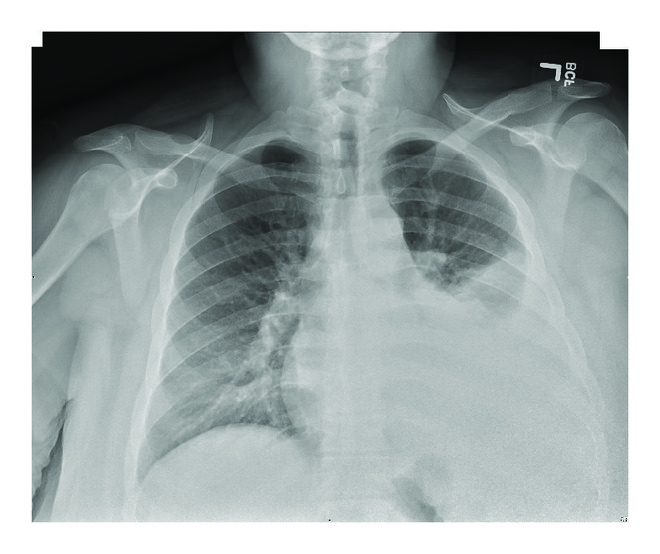

On examination, the patient was dyspneic. The temperature was 100.6 F, the pulse 105 beats per minute, the blood pressure 107/57 mmHg, the respiratory rate 20 per minute, and the oxygen saturation 100% on room air. Complete blood count was significant for a white cell count of 5.8 x 103 per μL. Comprehensive metabolic panel was significant for creatinine 0.76 mg/dL, lactate dehydrogenase 249 IU/L, albumin 3.3 g/dL, and total protein 6.7 g/dL. Chest X-ray (CXR) showed a large left sided pleural effusion with no consolidation (Figures 1(a) and 1(b)). Computed tomography (CT) of the abdomen and pelvis showed an enlarged left kidney with left staghorn calculus in the middle and lower portions of the kidney with an appearance suggestive of xanthogranulomatous pyelonephritis (Figures 2(a) and 2(b)). At this time, a diagnostic thoracentesis was performed yielding lactate dehydrogenase 656 IU/L, total protein 4.5 g/dL, amylase 30 U/L, triglycerides 50 mg/dL,, glucose 105 mg/dL, pH 7.56, and creatinine 0.8 mg/dL. Cultures and cytology of pleural fluid were negative. Pleural fluid was determined to be exudative by Light’s criteria as the lactate dehydrogenase was found to be greater than two-thirds the upper limits of our laboratory’s normal value [6]. Urine cultures obtained grew extended spectrum beta-lactamase Escherichia coli and the patient was started on appropriate antibiotic treatment. Urology service was consulted.

(a) A chest X-ray of the chest showing left side pleural effusion

After obtaining a nuclear medicine renal scan with intravenous technetium 99m MAG3 showing significant decrease in left kidney function, the urology consultant recommended and performed a robot-assisted nephrectomy. There was no fistula into the hemithorax identified at the time of nephrectomy. Following this, the patient had a complete resolution of the urinothorax with no evidence of recurrence on follow-up CXR.